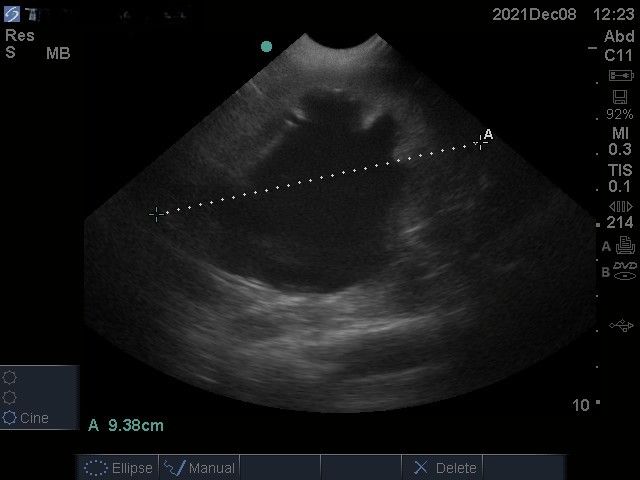

I have used the C11x probe (5-8MHz) which has been good for abdominal scanning of cats, small dogs and basic echocardiography. The depth obtainable (13cm) on the probe I have used is disappointing for large dogs. Having said that the image quality is reasonable. I have not been able to source new prices for this machine (if you are selling them please do get in touch!), however one machine I saw being sold second hand was well under £10,000 which suggests it’s starting price is <£10,000.

Images from the M Turbo